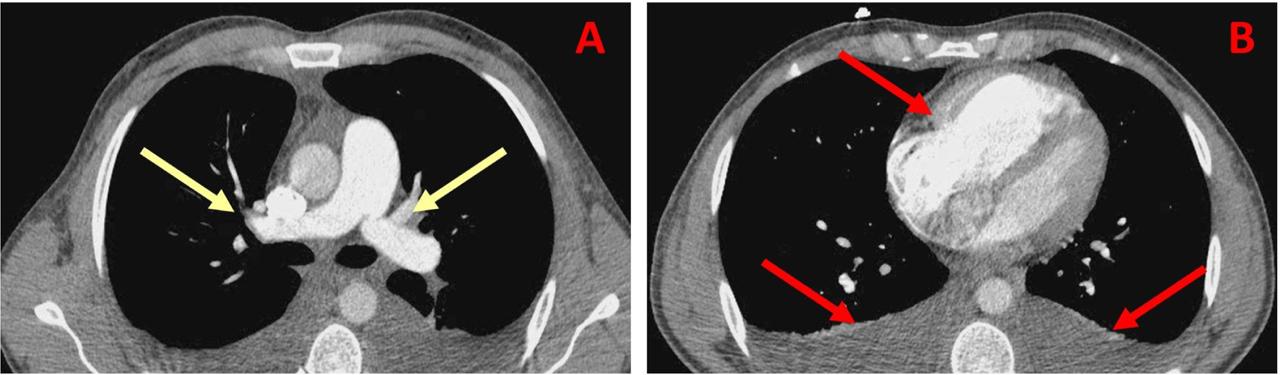

Thoracic computed tomography. Panel A. Thoracic CT scan with contrast revealed an optimal opacification of pulmonary arteries, without thrombi; Panel B. Dilated right heart chambers, mild pleural effusion and no pulmonary parenchymal pathology.